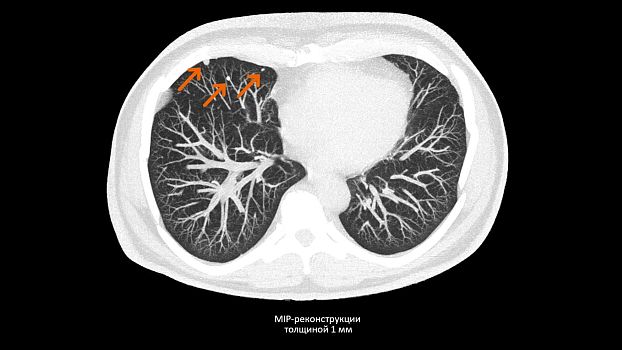

Позволяет выполнять сканирование с низкой лучевой нагрузкой, что очень важно для оптимальной заботы о пациенте. SOMATOM go.Up выполняет сканирование больших диапазонов за одну задержку дыхания с высоким пространственным разрешением.

SOMATOM go.Up позволяет проводить скрининговые исследования лёгких и толстой кишки, а также исследования сердца для оценки коронарного кальция. Благодаря субмиллиметровой коллимации SOMATOM go.Up обеспечивает высокое пространственное разрешение, тем самым повышая чувствительность диагностики в онкологии.